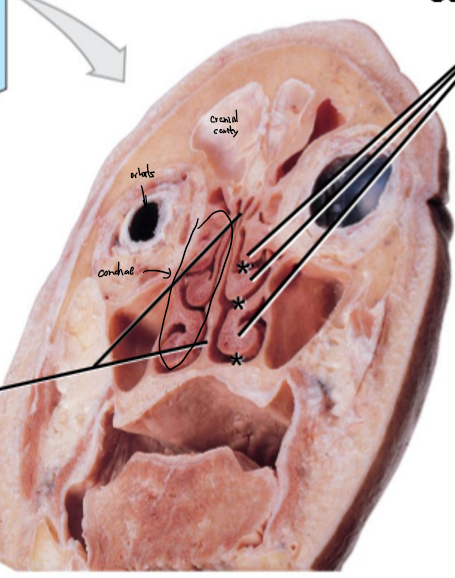

The superior and middle nasal conchae are made by the _____, and ______, also separating the _______ and _____

ethmoid, cribiform plate, cranial, nasal

A-D, colours from top to bottom

A: Maxillary air sinus

B: Ethmoid air cells

C: Perpendicular plate

D: Crista galli

E: Superior/middle nasal concha

Crista galli is a continuation of the _____ into cranial cavity

perpendicular plate